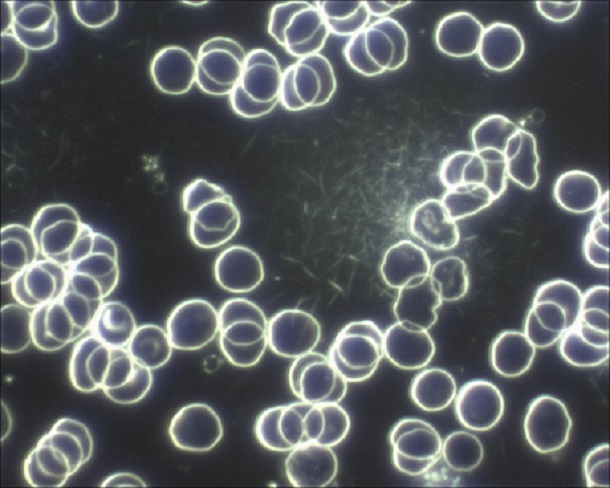

Hier ein Beispiel:

Beim Betrachten der beiden Aufnahmen sehen Sie den grundsätzlichen Unterschied. Um beim Beispiel „Himmel“ zu bleiben: Selbst wenn der Himmel wolkenlos ist, sieht man mit dem bloßen Auge nur die Sonne, vielleicht noch den Mond. Die umliegenden Sterne bleiben dem Auge verborgen – eine Metapher, die das grundsätzliche Prinzip der Dunkelfeldmikrokopie auch für Laien sehr anschaulich erklärt.

Das Besondere bei der Dunkelfeld-Diagnostik: Es gelangt nur das Licht ins Mikroskopbild, welches seitlich an den im Blut befindlichen Strukturen vorbei scheint. Somit heben sich alle Präparate im Blut durch das Mikroskopbild ab.

Man sieht also alles, was im Blut vorhanden ist, ohne dem Körper vorher etwas zufügen zu müssen, um diese sichtbar zu machen. Daher lassen sich auch lebende Organismen und Lebewesen schonend und sehr gut durch das Dunkelfeldmikroskop erkennen. Heute wird die Dunkelfeldmikroskopie nicht nur bevorzugt in der Biologie, beispielsweise bei der Beobachtung von mit dem bloßen Auge nicht sichtbaren Wasserlebewesen, verwendet, sondern immer öfter auch in der Medizin.

Für das Verfahren werden keine Kontrastmittel oder Fixierer benötigt, um mögliche Krankheitserreger oder andere Schadstoffe im Blut sichtbar zu machen – und genau hier liegt einer der größten Vorteile der Dunkelfeldmikroskopie. Da dem Blut vor der Betrachtung nichts zugeführt werden muss, nennt man dieses Verfahren auch Vitalblut-Untersuchung: man sieht das „lebende“ Blut und dessen Bestandteile.

In dieser Aufnahme habe ich für Sie einige Blutbestandteile beschrieben, die Sie im Dunkelfeld sehen können.

Das Blut wird hierbei bevorzugt aus dem Finger oder dem Ohrläppchen entnommen und es genügt oftmals ein einziger Tropfen.